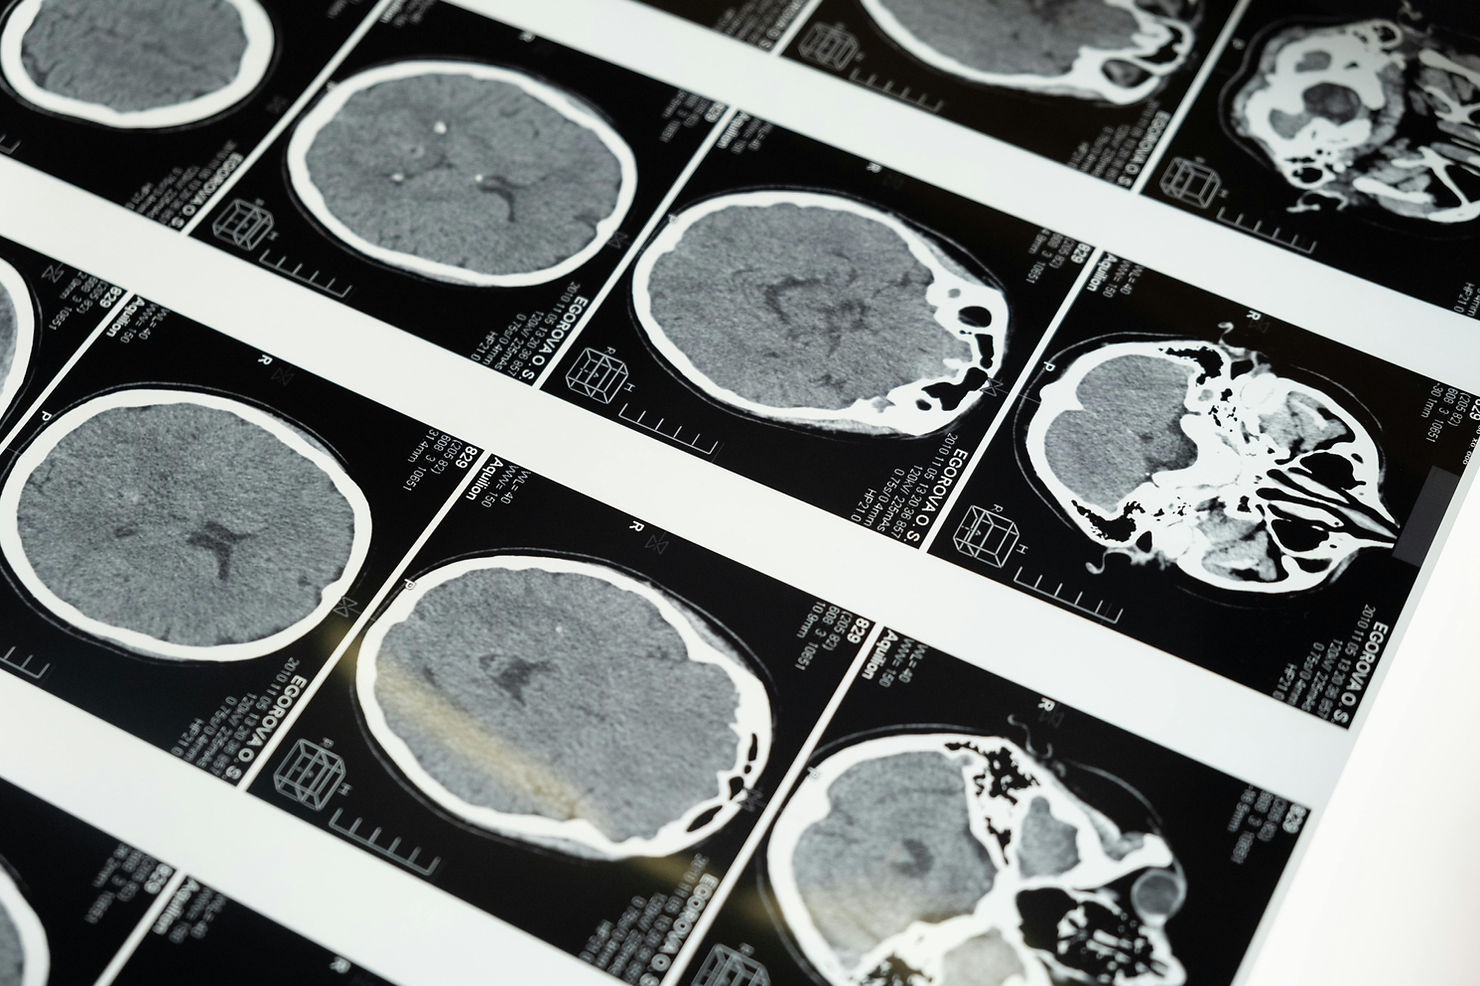

Since it came on the scene, magnetic resonance imaging (MRI), where a magnetic camera looks through the skull and captures pictures of a living brain, mountains of neuroimaging studies have been made by scientists eagerly delving into the most complex organ we have. It’s led to amazing discoveries and insights, and revolutionised our understanding of how we function.

In the study, the authors, who used magnetic resonance imaging to scan the brains of participants, found that only participants taking the pill had a slightly, yet noticeably, thinner ventromedial prefrontal cortex compared to those who were not on the pill (the effect was, however, reversible). Previous research has shown that the thicker that area is, the better emotional regulation works. Structural changes can also be observed inside the brains of people who go through menopause, alongside changes in brain connectivity and overall energy production, according to a study from 2021.